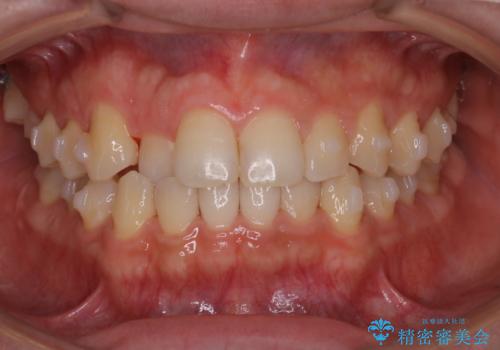

- 前歯のがたつきを主訴に来院されました。初診時、右上2番の口蓋側転位と右下7番の舌側傾斜が認められました。

インビザラインにてIPRと歯列弓拡大を行い、ゴム掛けで噛み合わせを改善する治療計画を立てました。

マウスピースの使用時間が短いため、シュミレーション通り進むか不安でしたが

治療期間1年で、主訴である前歯のがたつきを改善出来、

奥歯の噛み合わせも良くなりました。